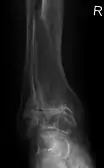

Diagnosis is made with reasonable certainty based on history and clinical examination.[42][43] X-rays may confirm the diagnosis. The typical changes seen on X-ray include: joint space narrowing, subchondral sclerosis (increased bone formation around the joint), subchondral cyst formation, and osteophytes.[44] Plain films may not correlate with the findings on physical examination or with the degree of pain.[45] Usually other imaging techniques are not necessary to clinically diagnose osteoarthritis.

Severe osteoarthritis and osteopenia of the carpal joint and 1st carpometacarpal joint.